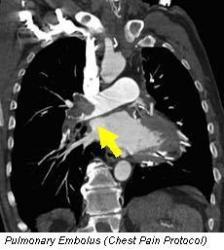

Before considering undergoing a cardiac CT, the most important step for the patient is to consult with their physician. This is because some cardiac CT uses are more appropriate than others, and the scan carries some risks from X-ray exposure and contrast dye administration.